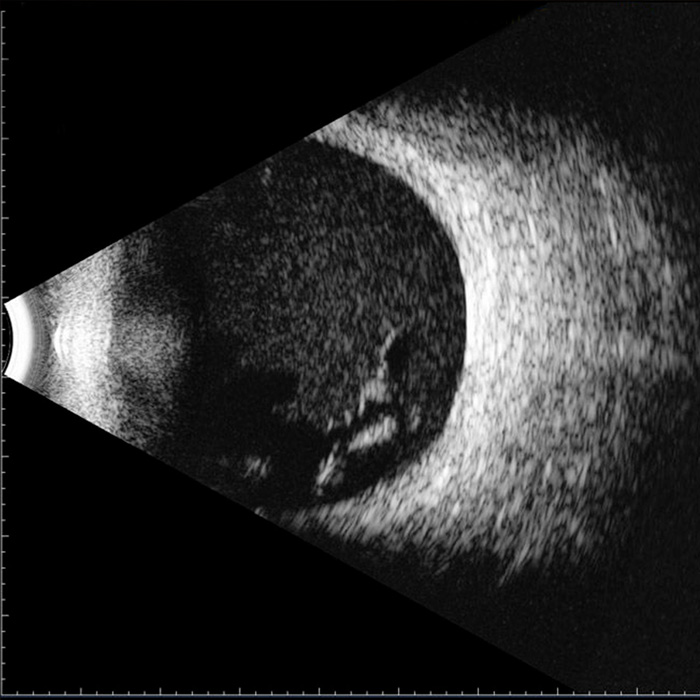

Veja maisEstudo da parte posterior do olho através do ultrassom de alta frequência.